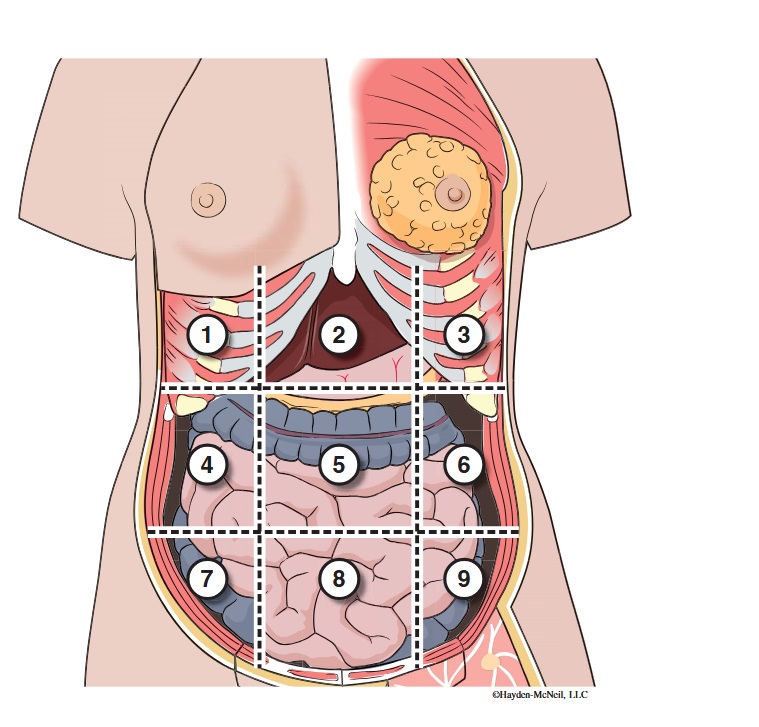

What abdominal region is labeled #1?

right hypochondriac

What abdominal region is labeled #2?

epigastric

What abdominal region is labeled #3?

left hypochondriac

What abdominal region is labeled #4?

right lumbar

What abdominal region is labeled #5?

umbilical

What abdominal region is labeled #6?

left lumbar

What abdominal region is labeled #7?

right iliac/ inguinal

What abdominal region is labeled #8?

hypogastric

What abdominal region is labeled #9?

left illiac/ inguinal

What organs are apart of the right hypochrondriac region?

right lobe of liver, gallbladder, right adrenal gland

What organs are apart of the epigastric region?

pyloric end of stomach, duodenum, pancreas

What organs are apart of the left hypochondriac region?

stomach, spleen, left adrenal gland

What organs are apart of the right lumbar region?

ascending colon, right kidney, portion of small intestine

What organs are apart of the umbilical region?

omentum, mesentery, small intestine

What organs are apart of the left lumbar region?

descending colon, left kidney, portion of the small intestine

What organs are apart of the right iliac/ inguinal region?

cecum of large intestines, appendix, right ovary

What organs are apart of the hypogastric region?

ileum, bladder, uterus

What organs are apart of the left iliac/ inguinal region?

sigmoid colon, left ureter, left ovary